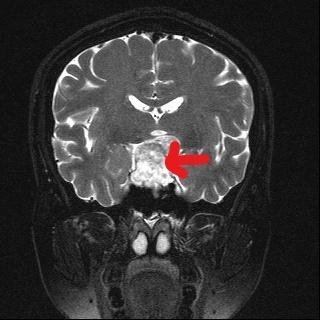

和大多数患者一样,家住郫都区的57岁的范女士也是如此。1年多前,范女士因面瘫行头部CT检查发现颅内鞍区占位。范女士当时认为占位病变不大,症状不重,又想到需要"开颅"动手术,这让她打起了退堂鼓,这一退便等了1年。直到2个月前,范女士开始出现视力下降的表现,并伴有头痛、头昏等不适,便到医院行头部MRI检查发现:鞍区占位较之前明显增大。这可将范女士愁坏了,立即和家人于6月份到郫都区人民医院神经外科就诊。本已做好开颅手术心理准备的范女士,却万万没有想到,医生既没有给自己开刀,也没有留下任何疤痕,就将颅内的肿瘤顺利切除了。

(术前检查发现肿瘤)

范女士入院后,神经外科全体医师综合讨论了患者病情,并为范女士制定了详细的神经内镜手术方案。完善相关术前准备后,6月25日,科主任任民副主任医师带领神经外科团队为患者在全麻下行"神经内镜经鼻蝶入路垂体瘤切除术+视神经减压术",实现了垂体肿物的内镜下全切,有效解除视神经压迫症状。患者术后3天,自觉视觉功能较术前有明显好转,垂体激素恢复正常,无明显脑脊液漏出现。通过神经外科医护团队的精心治疗和照顾,现已康复出院。

(术后检查显示肿瘤已切除)